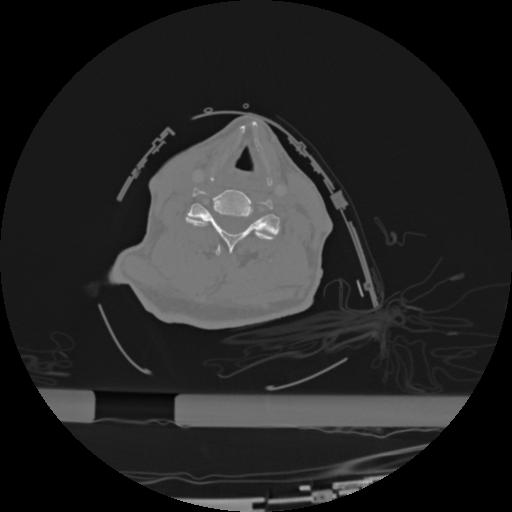

22 ANGIO,CE,Vol,0.5,ANGIO,,